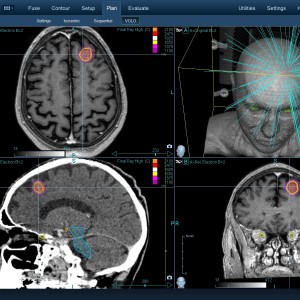

Στις παρακάτω φωτογραφίες θα δείτε παραδείγματα πλάνων θεραπείας καρκινικών όγκων με CyberKnife. Παρατηρήστε πόσο κοντά στους υγιείς ιστούς βρίσκονται οι καρκινικοί όγκοι που χρειάζεται να ακτινοβοληθούν. Μόνο με το CyberKnife και το προσωπικό πλάνο θεραπείας, μπορούν να ακτινοβοληθούν οι όγκοι χωρίς να πληγούν οι παρακείμενοι υγιείς ιστοί.

Μόνο με το CyberKnife και την κατάλληλη σχεδίαση της θεραπείας από έμπειρο νευροχειρουργό, μπορεί να ακτινοβοληθούν οι όγκοι χωρίς να επηρεαστούν από την ακτινοβολία οι υγιείς ιστοί. Αυτό εξασφαλίζει τη μέγιστη δυνατή απόδοση της ακτινοχειρουργικής θεραπείας των όγκων.

Ο νευροχειρουργός Λέκας Λεωνίδας έχει τη μεγαλύτερη εμπειρία στην Ελλάδα στο σχεδιασμό θεραπειών στερεοτακτικής ακτινοχειρουργικής όγκων του εγκεφάλου και του νευρικού συστήματος σε CyberKnife. Ο σχεδιασμός του πλάνου θεραπείας προϋποθέτει άριστη γνώση της ανατομίας και της απεικόνισης του κεντρικού νευρικού συστήματος έτσι ώστε να επιτευχθεί το βέλτιστο θεραπευτικό αποτέλεσμα με τη μέγιστη δυνατή προστασία των ευαίσθητων δομών.

Με κόκκινο χρώμα περιγράφεται η περιοχή του όγκου.

Με μπλε, κίτρινο και πράσινο χρώμα περιγράφονται οι υγιείς ιστοί που δεν πρέπει να ακτινοβοληθούν.

Παρατηρήστε πόσο κοντά βρίσκεται ο όγκος με τους υγιείς ιστούς.

Παρατηρήστε τις πάρα πολλές δέσμες του CynerKnife που ακτινοβολούν τους όγκους από διαφορετικές γωνίες ώστε να μην προσβληθούν από την ακτινοβολία οι υγιείς ιστούς.